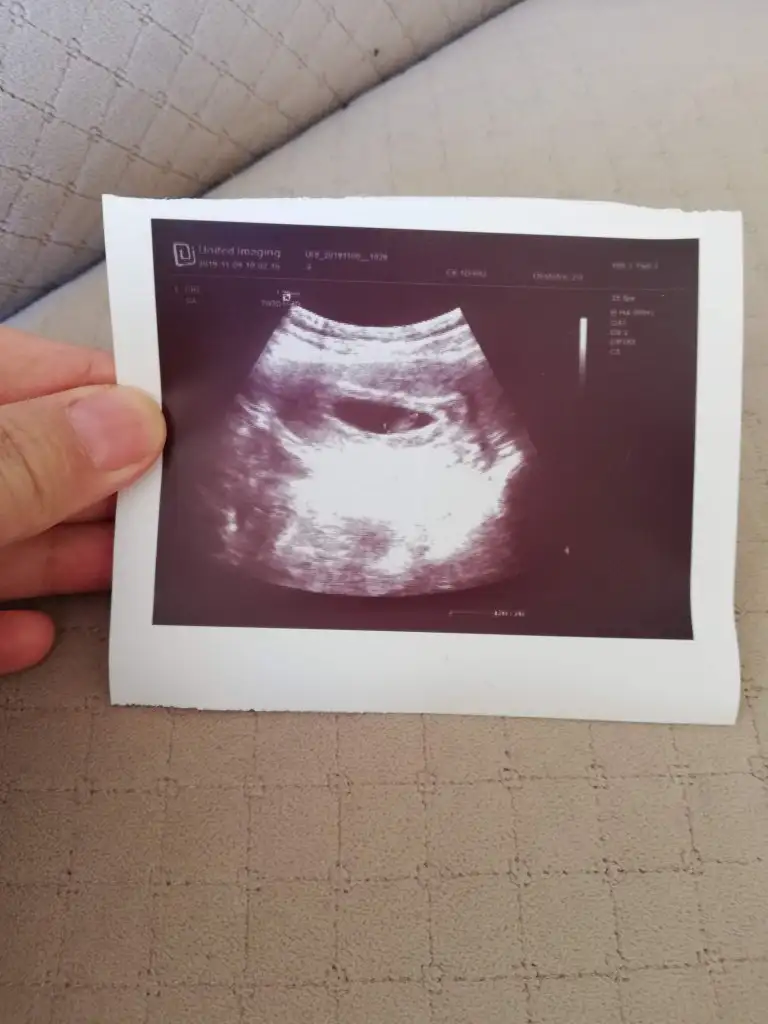

Benimki ne acaba ☺☺

Ilk 9cu hafta ikincisi 12ci hafta